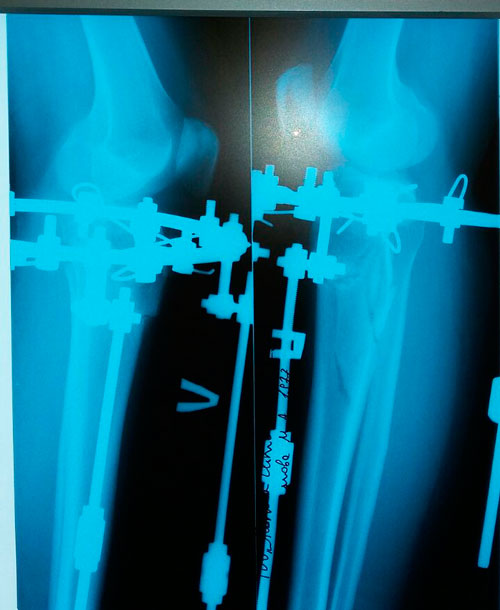

Дата операции 14.03.2017г.

Исходник - 39 лет.

Ротация (двухсторонняя)

РЕНТГЕН ДО ОПЕРАЦИИ